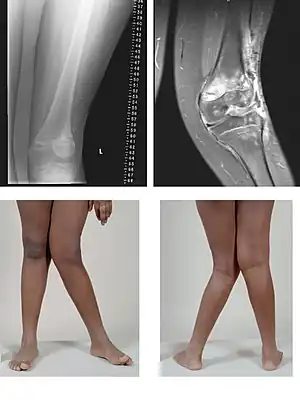

| Valgus deformity of the knee (genu valgum), seen in MRI and photograph | |

A valgus deformity is a condition in which the bone segment distal to a joint is angled outward, that is, angled laterally, away from the body's midline.[1] The opposite deformation, where the twist or angulation is directed medially, toward the center of the body, is called varus. Common causes of valgus knee (genu valgum or "knock-knee") in adults include arthritis of the knee and traumatic injuries.

Knee arthritis with valgus knee

Rheumatoid knee commonly presents as valgus knee. Osteoarthritis knee may also sometimes present with valgus deformity though varus deformity is common. Total knee arthroplasty (TKA) to correct valgus deformity is surgically difficult and requires specialized implants called constrained condylar knees.